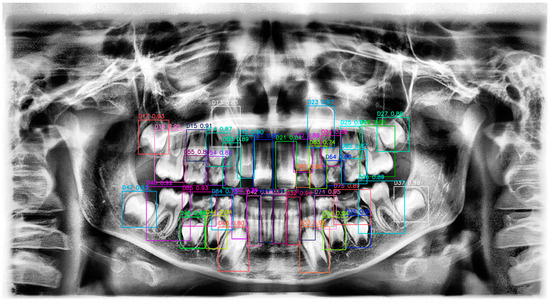

Evaluation of the Performance of a YOLOv10-Based Deep Learning Model for Tooth Detection and Numbering on Panoramic Radiographs of Patients in the Mixed Dentition Period

2.4. Ground Truth Labeling